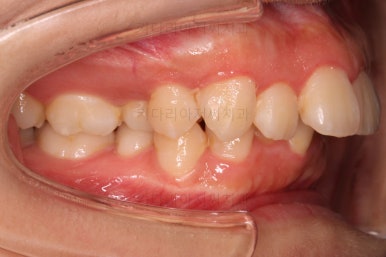

부산무턱교정치과 초진 시 입안의 모습입니다.

전반적으로 치열이 삐뚤고요. 아랫니가 윗니보다 뒤쪽으로 많이 가려져 있죠.

그래서 앞에서 봤을 때 아래 앞니가 거의 보이지 않는 상태인데요.

이런 교합을 "과개교합"이라고 표현합니다.

전반적인 교합, 치열, 과개교합, 튀어나와 보이는 앞니 등을 개선해줘야겠네요.

마찬가지로 초진 시 얼굴모습 입니다.

웃거나 말할 때 튀어나온 앞니가 강조되어 보여 입은 더 나와 보입니다.

아래턱이 작아서 옆모습에서 무턱 느낌이 들고요.

상대적으로 입은 나온 돌출입 양상입니다.